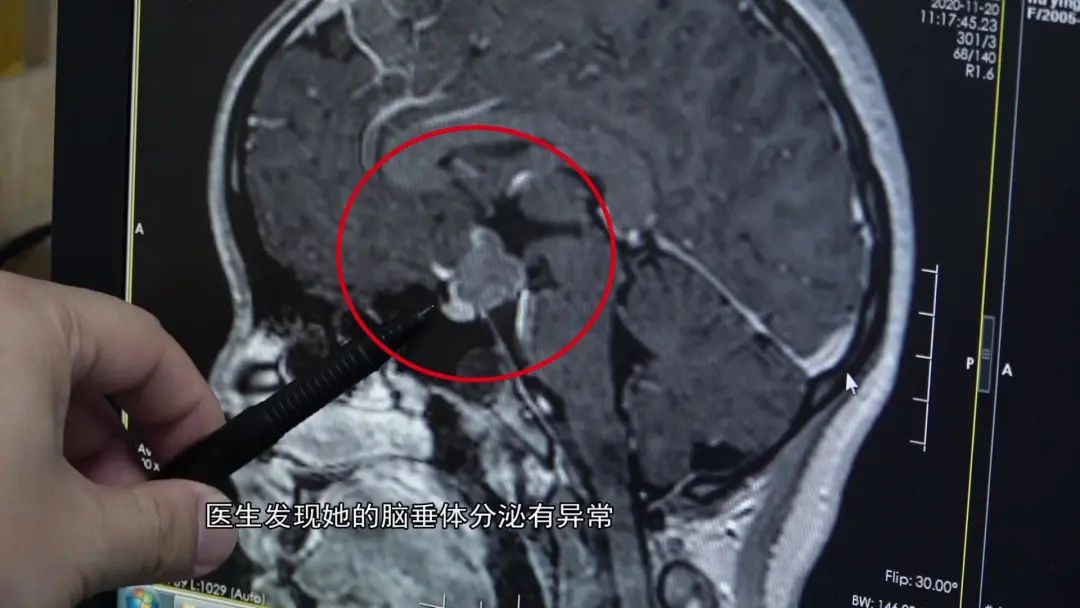

直到有一次检查,医生发现她的脑垂体分泌有异常。

通过脑部CT,发现脑部有个阴影。

小花(化名)颅内鞍区,

有先天发育残留组织所形成的肿瘤,

是影响内分泌,

造成她停经的主要原因。